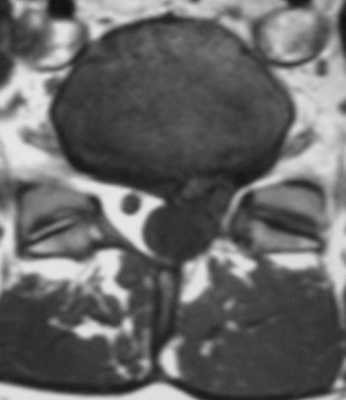

Фораминальная рецидивная грыжа 5 мм. Дискография.

Сдавление корешка L4 в корешковом канале, несмотря на малые размеры грыжи. Эпидурография.